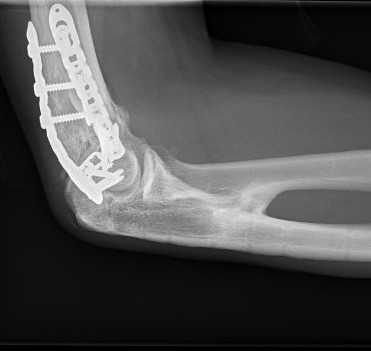

Xray

Radio-ulna synostosis

CT

Define anatomical location of the HO prior to surgical excision